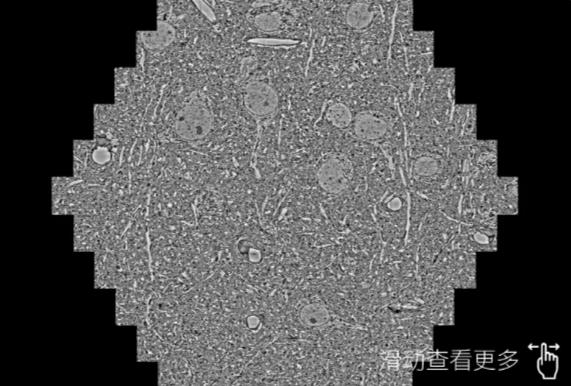

鼠脑切片。左图使用萍乡蔡司萍乡扫描电镜MultiSEM706对165μmx143pm面积区域成像,耗时仅需1.5秒。右图为鼠脑切片中30μm区域放大效果。样品由芝加哥大学B.Kasthuri提供。

使用蔡司高速萍乡扫描电镜MultiSEM对1mm²人脑皮层组织进行高分辨成像,并对其中的各种细胞结构进行三维重构分析。左图展示了2x3mm²组织平面中锥体神经元的三维重构效果。右图显示了局部体积神经元三维重构。图像由哈佛大学chtman实验室提供,渲染图由D. Berger 制作。